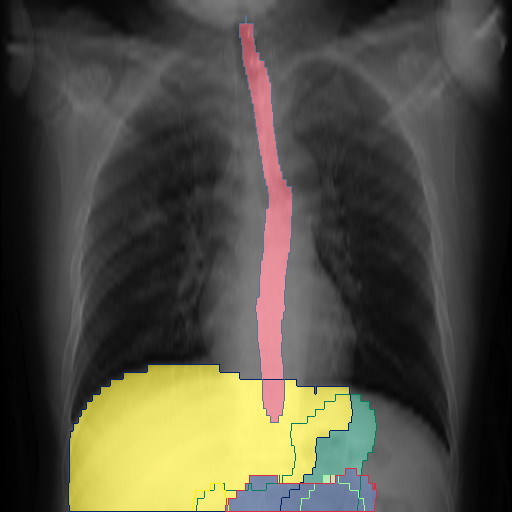

We show qualitative results for frontal projections in Fig. 2. We show a subset of classes belonging to the supercategories lungs, vascular systems, bones, and abdomen/digestive system. The predictions show minor deviations at the boundaries of the individual classes of the respiratory and vasculature system, while some inaccuracies become visible in the abdominal area. The qualitative results for the lateral projections are displayed in Fig. 2. Akin to the frontal view, the predictions show smoother borders but align with the ground truth. Apart from this, the segmentations provide matching insights on the thoracic anatomy with a slight deviation from the ground truth for both frontal and lateral views.

We display qualitative results in Fig. 3. The annotators tend to be content with most annotations. There are edits at the extensions of the esophagus, trachea, and aorta and corrections of the lower ribs. There is little consensus for classes in the abdominal area, such as the stomach, as seen on the right of Fig. 3 . In contrast, the annotators often align for bone classes.